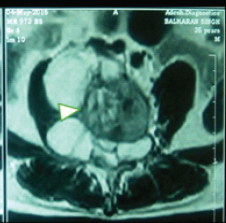

Surgical Management of Pott’s Paraplegia in a 27-Week Pregnant Woman with Continuation of Pregnancy: A Case Report

Hamza Shaikh , Aditya Chouhan

………………………………p.48-53